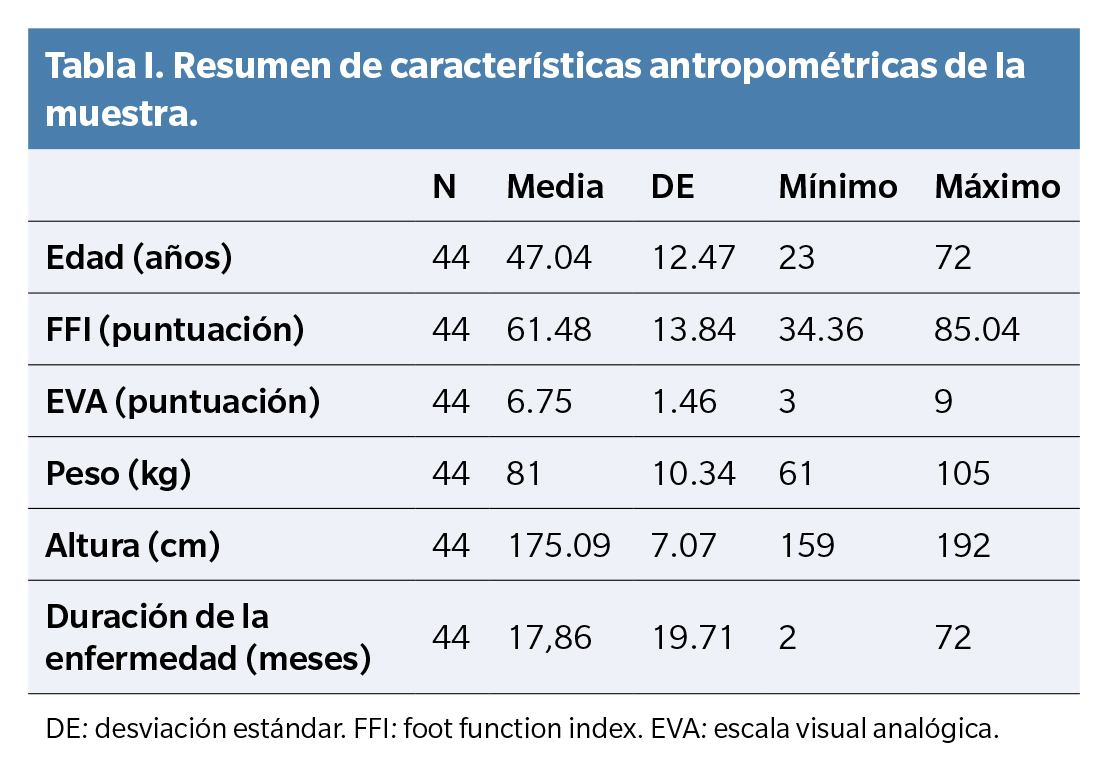

El total de la muestra estudiada fue de 44 pacientes. La edad media de los pacientes fue de 47.05 ± 12.34 años. La puntuación media en la escala EVA fue de 6.75 ± 1.45. La puntuación de la función en la escala FFI fue 61.49 ± 13.69. El grosor medio de la fascia plantar fue de 5.97 ± 1.08. El peso corporal medio fue de 81 ± 10.35 kilogramos y la talla de 175.09 ± 7.07 centímetros. En 15 sujetos la enfermedad apareció por primera vez, en 13 fue una recurrencia y en 16 se consideró crónica. 4 sujetos eran sedentarios, 26 eran activos y 14 eran deportistas. La duración media de la enfermedad en meses fue de 9.513 ± 6.58. Treinta y dos pacientes habían recibido tratamiento previo y 12 no. Nueve presentaron biconvexidad de la fascia plantar y 35 no (Tablas 1, 2 y 3).

Los factores pronósticos en la FP se analizan con frecuencia para proporcionar información sobre la medida en que los pacientes se beneficiarán de las diferentes modalidades de tratamiento. El engrosamiento de la fascia plantar es de particular interés, ya que es una manifestación prominente y frecuente de la FP y se puede evaluar cuantitativamente. En este estudio descriptivo, el grosor medio de la fascia plantar en hombres con FP fue de 5.97 ± 1.08 mm, y los predictores significativos de un mayor grosor fascial incluyeron no haberse realizado tratamiento previo, una baja talla, una alta puntuación en la escala FFI y un corto tiempo de evolución de la enfermedad.